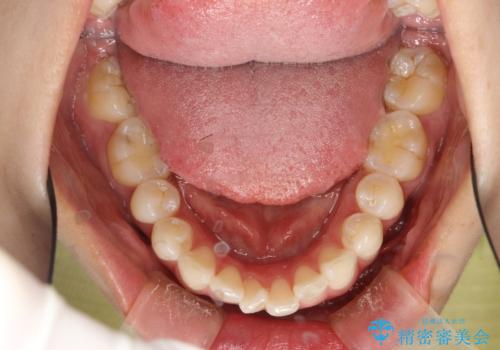

後戻りした歯並びをきれいにしたい

- ワイヤーで矯正した後戻りをマウスピースで治そうとしたが、使えなかったため再度ワイヤー矯正希望で来院されました。

装置はハーフリンガルを選択しています。

矯正としてはマウスピースでできましたが、患者さんの希望でワイヤー(ハーフリンガル)で矯正を行いました。

右下1が歯肉退縮していたため、アーチを拡げないように歯と歯の間を削って隙間をあけて並べています。